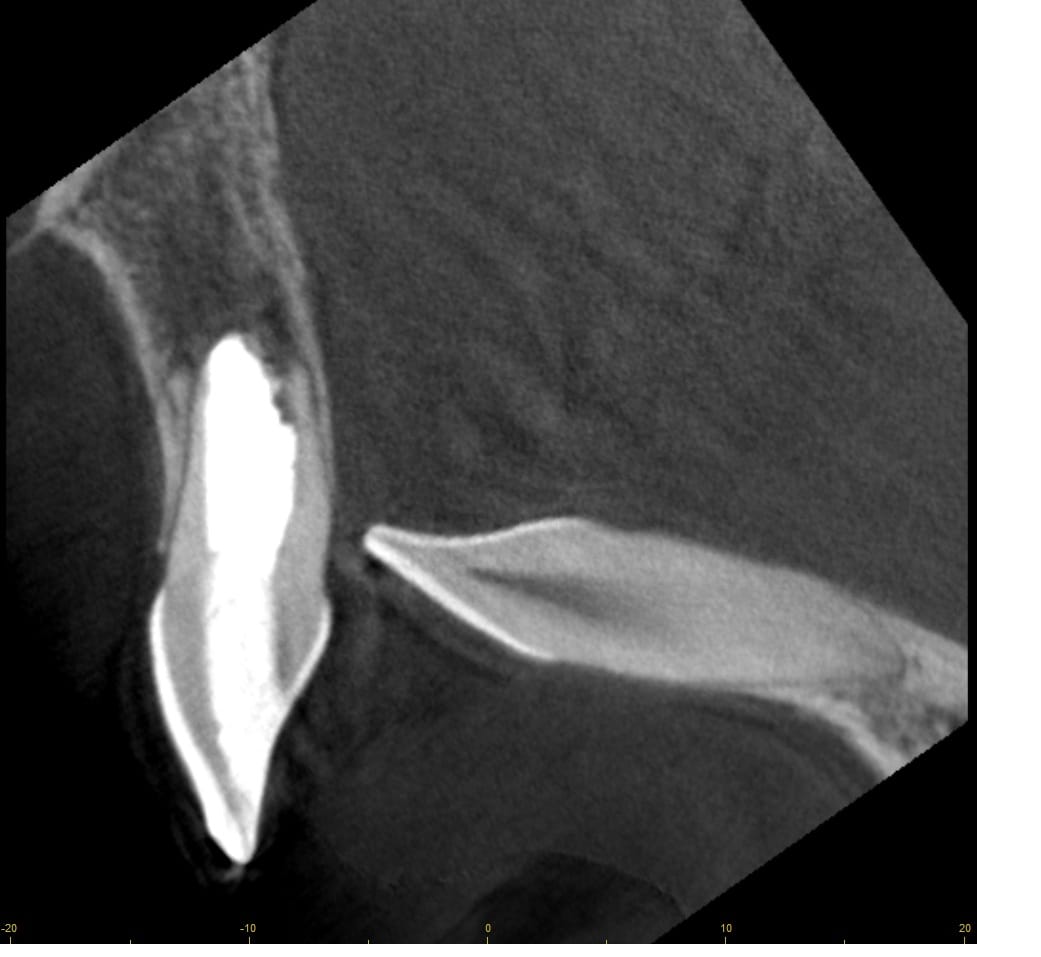

Bal oldalon egy hagyományos gyökérkezelés eredménye látható, míg jobbra ugyanazon fog mikroszkópos módszerrel végzett helyreállítása

Mikroszkóppal akár 20-szoros nagyításban a rejtett, szűk, csatornák pontos feltárása, betört tűk, régi gyökértömés eltávolítása is lehetséges. A mikroszkópos gyökérkezelés olyan esetekben is megoldást jelenthet, amelyeket korábban húzásra ítéltünk volna.